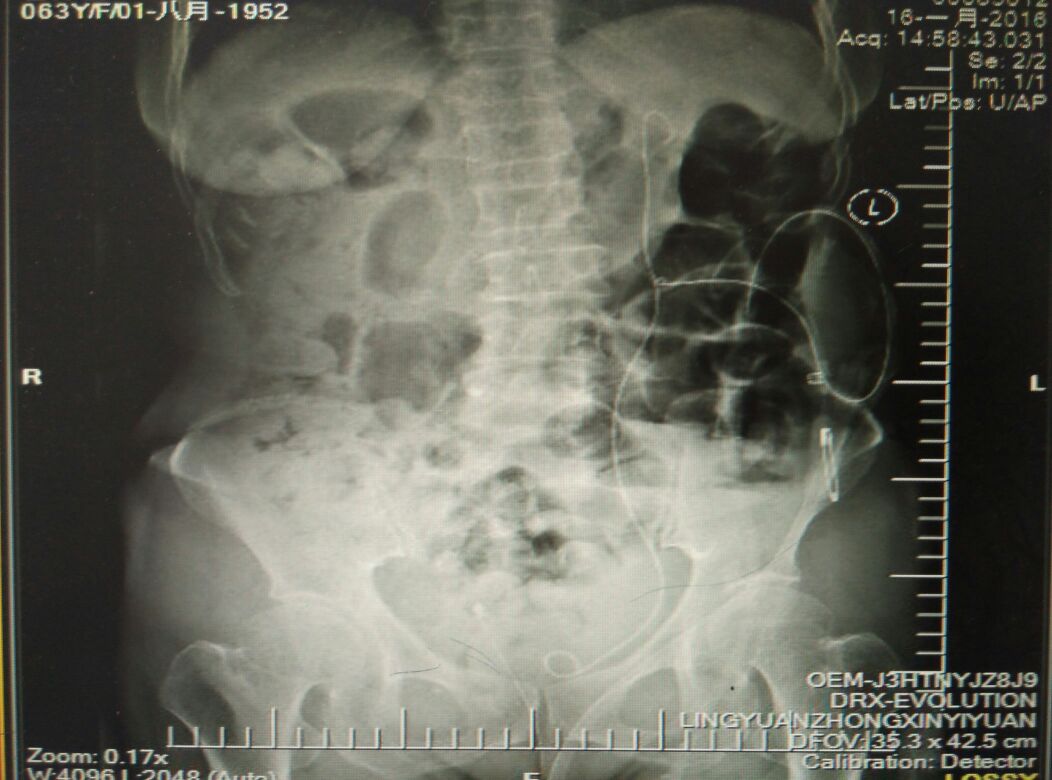

右肾结石介入治疗